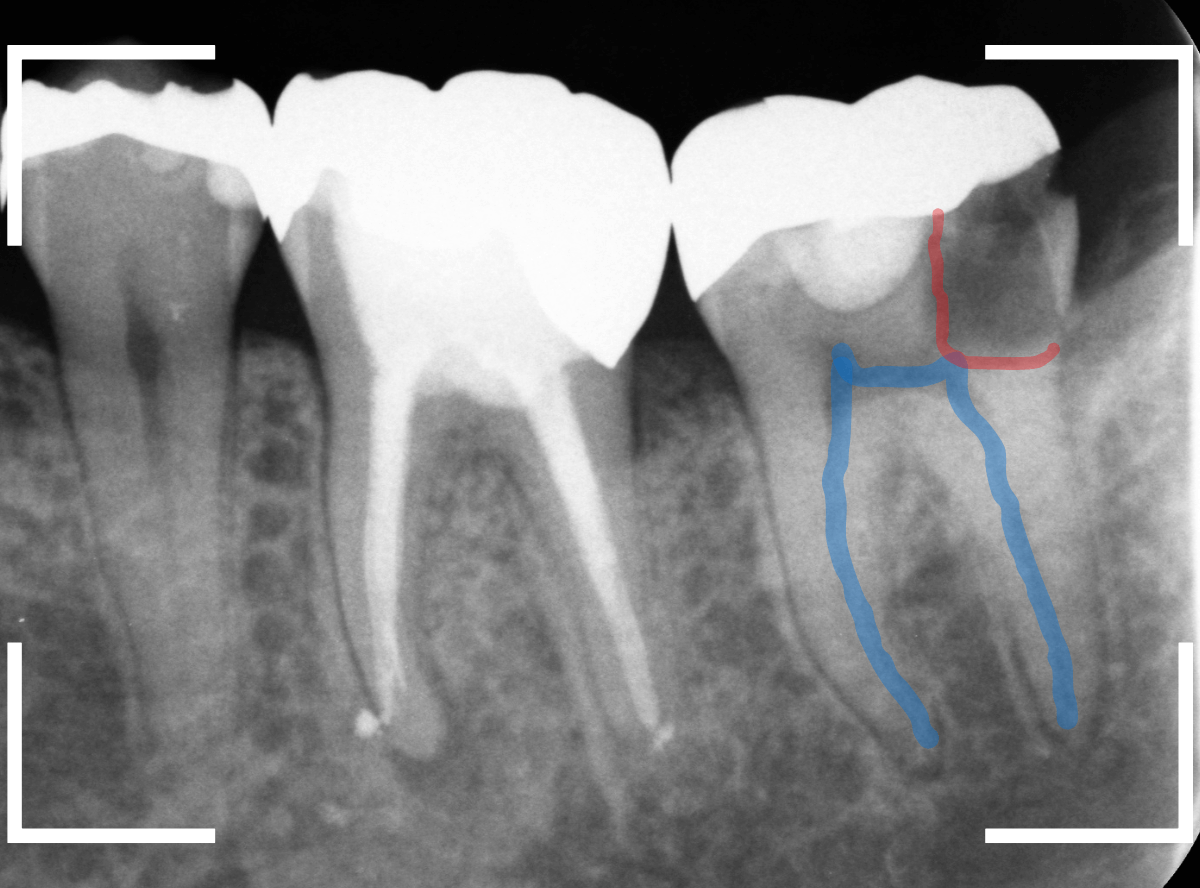

レントゲン写真で確認します。

やはり、奥歯の端が大きな虫歯になっています。

青いラインが歯の神経、赤いラインが虫歯です。

レントゲン写真上では虫歯が神経まで達しているように見えます。

これは、神経を取らないとダメかもしれません。